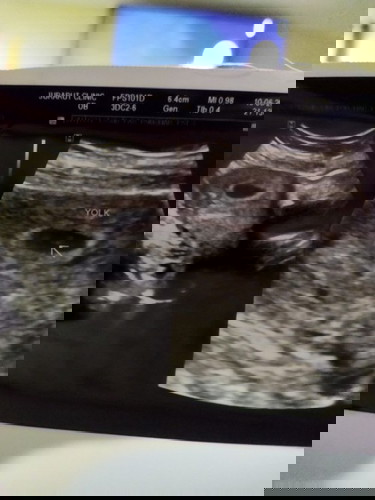

ไปซาวด์มาคุณหมอแจ้งว่าครรภ์อ่อนมาก อีก2สัปดาห์ค่อยมาฝากครรภ์ใหม่ เลยไม่ทราบว่าที่เห็นคืออะไรประมาณกี่สัปดาห์ ***คุณแม่ท่านไหนพอทราบช่วยบอกหน่อยคะ